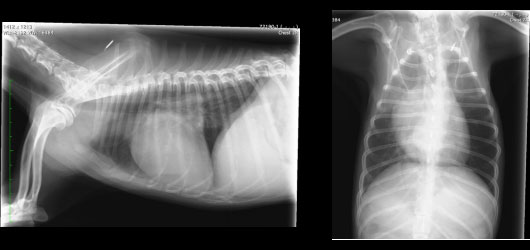

レントゲン検査でも肺の状態や大きかった心臓も縮小しています(図7参照)

図7